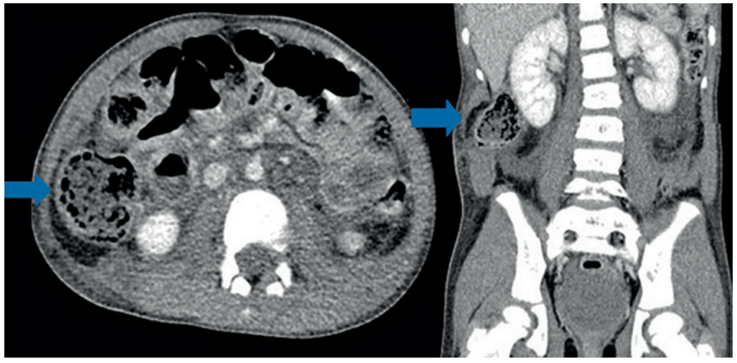

Masculino de 5 años quien sufre accidente de tránsito como ocupante de automóvil que colisionó frontalmente con un tractocamión. Ninguna víctima mortal en el accidente. Fue evaluado inicialmente en un hospital de primer nivel donde lo encuentran con estabilidad hemodinámica, pero con hematuria macroscópica, por lo que remiten. Se practicó TC abdominal (Figura 4) que diagnosticó hernia traumática de la pared abdominal, por lo que se programó para cirugía.

En el procedimiento quirúrgico se encontró ruptura de la fascia y de los músculos recto abdominal, oblicuos interno, transverso y oblicuo externo, conformando un defecto de 6 cm de longitud, con contenido herniario de colon ascendente y despulimiento de su serosa, sin perforación de asas ni otras lesiones asociadas. Se corrigió la hernia con cierre primario de forma videoasistida y presentó buena evolución posquirúrgica, dando de alta a los tres días de la cirugía. Seguimiento a 36 meses sin complicaciones ni recidiva de la hernia.